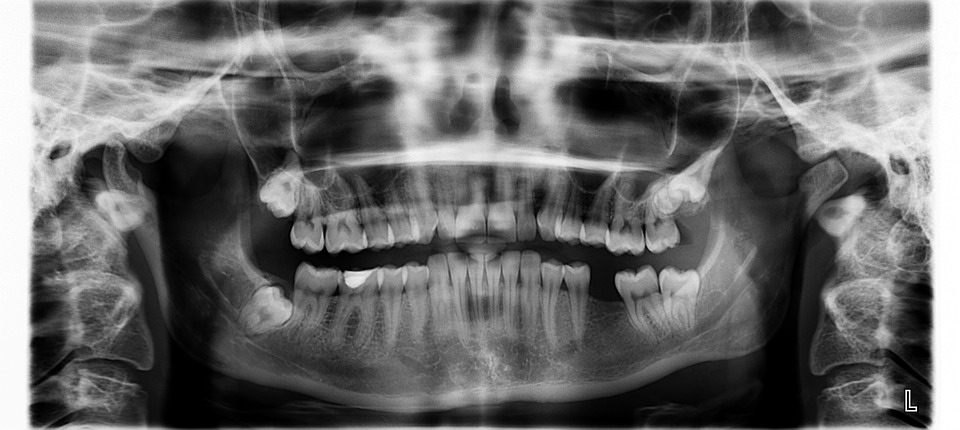

Radiografiile dentare sunt indispensabile în momentul efectuării unui control stomatologic. Medicul dentist se folosește de această imagine a dinților pentru a putea evalua în mod corect starea sănătății orale a pacientului. Radiografiile dentare panoramice folosesc un nivel foarte scăzut de radiații pentru a captura imagini ale interiorului cavității dentare, oferind o imagine exactă a dinților și gingiilor.

Deoarece dorim ca tratamentele noastre să fie efectuate de fiecare dată cu exactitate, am ales să dotăm clinica cu un centru complet de radiologie dentară. Serviciile noastre de radiologie dentară includ: radiografii panoramice, radiografii intraorale și scanări asistate de computer tomograf, realizate cu ajutorul aparaturii noastre de ultimă generație. Acest centru oferă pacienților confortul de a avea în clinică toate cele necesare pentru un diagnostic exacte.

Printre beneficiile acestui tip de diagnosticări sunt:

1. Identificarea cariilor de pe dantura inferioară și superioară

2. Stabilirea tipurilor de infecții prezente în cavitatea bucală

3. Investigarea fracturilor, anomaliilor osoase și a tumorilor

4. Obținerea unei imagini complete ale maxilarului

5. Asigurarea că tratamentele endodontice au fost efectuate corespunzător prin filmele intraorale

6. Efectuarea radiografiei și a CBCT (tomografie computerizată cu fascicul conic) pentru a asigura pacienții că implanturile dentare și augumentarea osoasă s-a realizat corespunzător

7. Controlul lucărilor protetice pentru a ne asigura că acestea sunt fixate corespunzător și nu fac presiune asupra implanturlor (acolo unde este cazul)